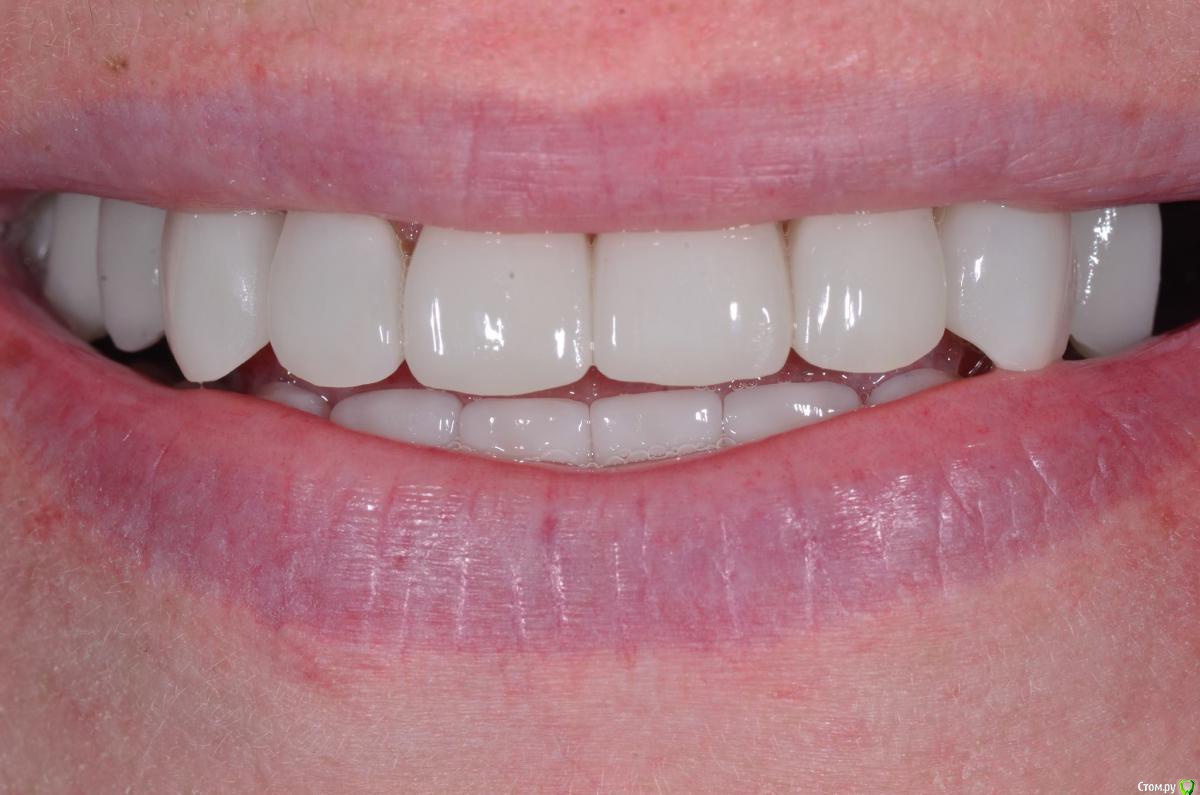

togrul Опубликовано 4 апреля, 2016 Поделиться Опубликовано 4 апреля, 2016 Добрый вечер коллеги. Восстановили зубы безметалловыми коронками Емах зубы и Циркон наслоением на имплантатах. 9 Ссылка на комментарий

togrul Опубликовано 5 апреля, 2016 Автор Поделиться Опубликовано 5 апреля, 2016 Все фотографии в день фиксации. 3 Ссылка на комментарий